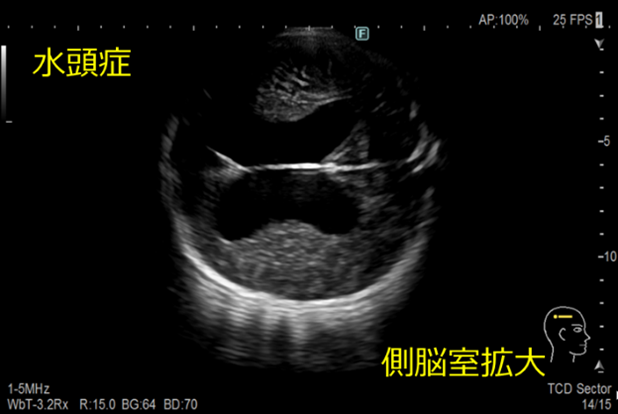

経頭蓋超音波検査

頭蓋骨早期癒合症の有無、頭蓋内の病変の有無や性状などについて観察しています。

水頭症とは

髄液が頭蓋内腔に過剰に貯留した状態のことです。

脳室拡大、頭蓋内圧亢進、脳実質の圧迫などが見られます。